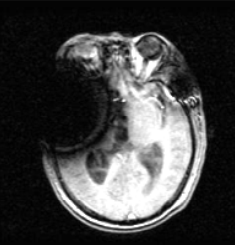

51 是: (A) T1WI(T1 weighted image) (B) T2WI(T2 weighted image) (C) FLAIR(fluid attenuation inversion recovery) (D) DWI(diffusion weighted image)

52 承上題,這張影像的 TR,TE 最可能是: (A) TR:4000 msec、TE:120 msec (B) TR:500 msec、TE:20 msec (C) TR:800 msec、TE:200 msec (D) TR:50 msec、TE:20 msec